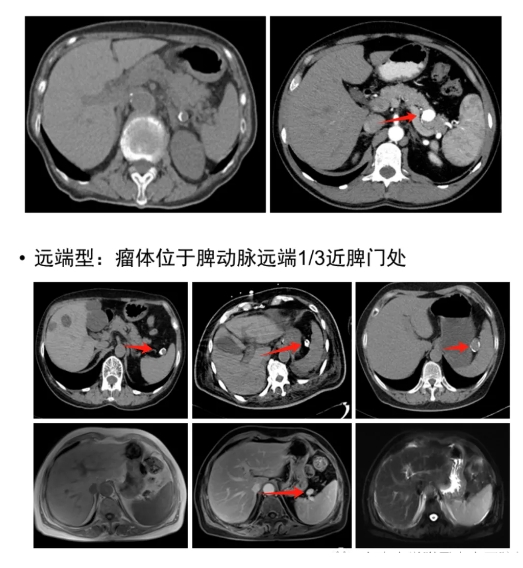

(1)脾动脉瘤未破裂影像学表现